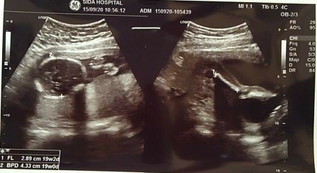

พอดีท้องแรกคาะ ดูไม่เป็น อยากทราบว่าคือส่วนไหนของน้อง หมอแค่บอกวาาน้องหันก้นให้หมอ ดูยังไงก็ดูไม่ออก ดูไม่เป็น ขออนุญาติถามน่ะค่ะแม่ๆ

ซ้ายศีรษะ ขวาส่วนขา ค่ะ